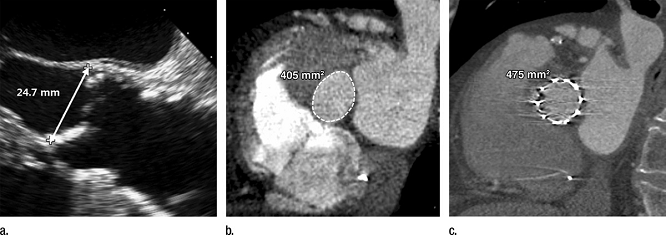

图10 (a,b)TAVR术前采集的图像(a)经胸壁超声心动图(b)84岁,男性,严重主动脉狭窄症状,多排螺旋CT检查。二维超声心动图测量主动脉环直径24.7mm,选择26mm直径的经导管心脏瓣膜(面积132.75px2),尽管主动脉环在CT图像上的面积测量值是100px2,通常根据这个测量值,会推荐使用23mm的经导管心脏瓣膜。(c)术后CT图像上显示环形但没有完全展开的经导管心脏瓣膜,原因是在单一的二维图像上测量椭圆形结构,明显高估瓣膜的尺寸。